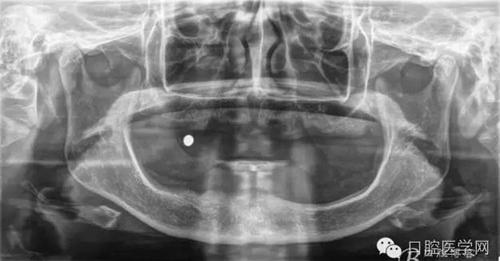

種植覆蓋全口義齒X線顯示骨量條件可以,準備從下頜兩側大概3、4的位置植入植體。

種植覆蓋全口義齒判斷位置。